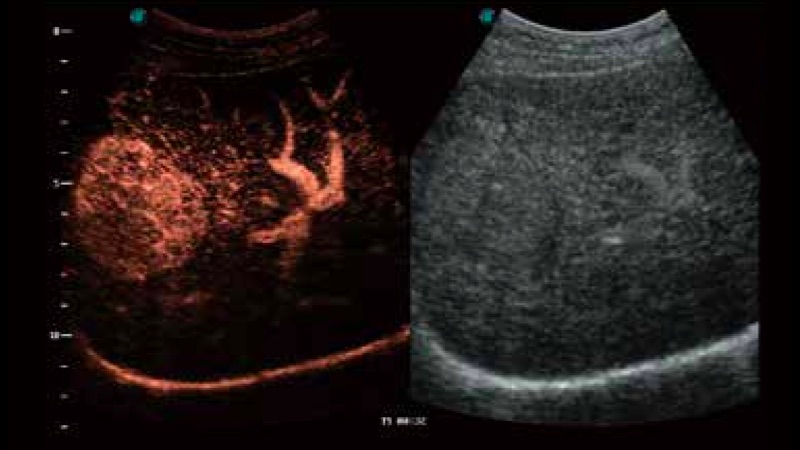

開(kāi)立醫(yī)療通過(guò)不斷的技術(shù)創(chuàng)新,為大眾的生命健康提供持續(xù)關(guān)愛(ài)。P12 Plus采用全新一代超聲成像平臺(tái),新平臺(tái)旨在將真實(shí)還原組織解剖結(jié)構(gòu)作為首要目標(biāo)。平臺(tái)采用全新集成化硬件模塊,搭載新一代芯片,系統(tǒng)性能得到大幅提升,為您的診斷提供了豐富的臨床信息。優(yōu)異的圖像表現(xiàn),豐富的探頭配置,全面的應(yīng)用功能,為您日常診斷提供了可靠的助手。

彩色多普勒超聲診斷系統(tǒng)